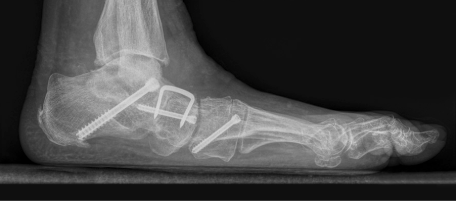

- W przypadkach zaawansowanego płaskostopia, gdy metody zachowawcze nie przynoszą efektu, konieczne może być leczenie operacyjne. Można przeprowadzać osteotomie korygujące, przeszczepy ścięgien lub stabilizacje stawów skokowych.